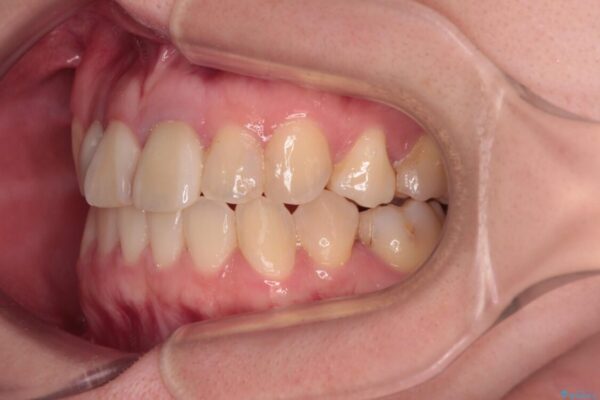

治療前

• 虫歯治療ついでに歯並びの後戻りを改善 インビザラインによる矯正治療 治療前画像

奥歯が痛いとのことで来院された患者様です。

上顎親知らず周辺の炎症と、神経組織の失活した歯の炎症による痛みが認められたため、親知らずの抜歯と根管治療を行いました。

根管治療を行った歯はクラウンによる補綴治療が必要となりますが、高校生の頃に行った矯正治療の後戻りも気になるとのことで、補綴治療を行う前に矯正治療を行うこととしました。

後戻りは軽度であり、インビザラインにて歯列を整え、その後にオールセラミッククラウンにて補綴治療を行うこととしました。